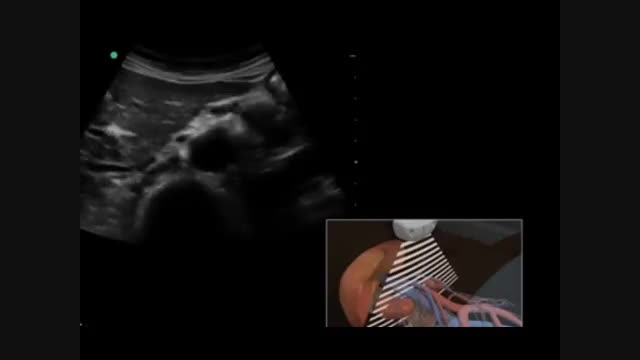

پخش صدا سونوگرافی کلیه اشتراکگذاری لیست پخش ۰ نظر ۰ نظر دانلود دانلود ویدیو دانلود ویدیو ۲.۴۷ مگابایت گزارش تخلف بیشتر گزینههای بیشتر لیست پخش لایکها گزارش تخلف ۱ لایک aysa منتشر شده در تاریخ ۱۳۹۵/۰۹/۲۵ این کانال دنبال شد دنبال کردهاید دنبال کردن این کانال دنبال کردن دراین ویدیو سونوگرافی کلیه را مشاهده خواهید کرد . ادامه علم و فن آوری نظرات لبخند لبخند لغو ثبت نظری برای نمایش وجود ندارد.